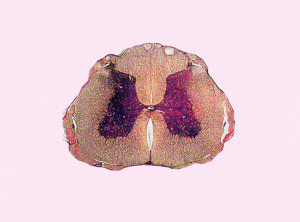

脊髓前動脈綜合症脊髓前動脈起源於兩側椎動脈顱內段,多在延髓腹側合併成1支,沿著脊髓前正中裂下行供應脊髓全長。在前正中裂內每1.0 cm的脊髓前動脈分出3-4支溝動脈。這些溝動脈不規則左右交替深入脊髓,供應脊髓前2/3區域的血液,包括脊髓前角、側角、灰質連合、后角基部、前索、側索。因此,當其發生閉塞時,則出現痛溫覺喪失而深感覺存在的特異性感覺障礙的臨床表現,同時出現肢體運動障礙及膀胱直腸功能障礙。溝動脈系終末支,容易發生缺血性病變,脊髓前動脈下行過程中與脊髓後動脈及眾多的根動脈形在吻合支豐富的冠狀動脈環,相鄰根動脈吻合處或交界處是血液供應的薄弱點,一般認為在T4及Ll段。因此,易發生缺血性損傷。但目前認為C4節段也是易發生缺血性脊髓血管病的危險帶。脊前綜合徵發病特點包括:①多見於中老年;②急性起病,症狀在幾小時內達高峰;③一般以劇烈神經根痛為首發症狀,隨後在幾小時內出現癱瘓,癱瘓多對稱,少部分可不對稱;④病灶平面以下分離性感覺障礙(痛溫覺障礙而深感覺存在);⑤上頸髓受累,可出現呼吸困難、根性疼痛、劇烈的根痛可為脊髓前動脈綜合徵。